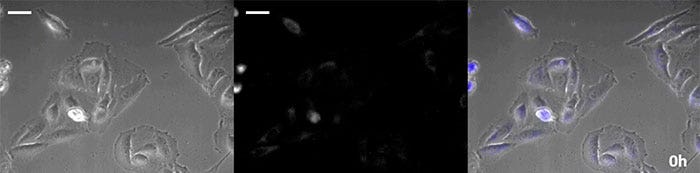

Luciferin vom Coelenterazin-Typ hat eine besonders hohe Leuchtkraft, aber da es in der Zelle innerhalb kurzer Zeit oxidiert, ist eine rechtzeitige Zugabe für Langzeitbeobachtungen unerlässlich. Um dieses Problem zu lösen, haben wir die Zellen mit hochintensivem lumineszierendem Protein perfundiert und das Coelenterazin über ein automatisches Gerät zugegeben, so dass die Lumineszenz kontinuierlich überwacht werden konnte. So konnten wir das Lumineszenzbild in Kombination mit der Phasenkontrast-Bildgebung 24 Stunden lang beobachten (Abbildung 4).

0 Stunden

Abbildung 4-1 0 Stunden